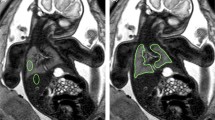

Anonymised fetal MRI data were exported from the hospital PACS (Dedalus HealthCare, Bonn, Germany). Manual segmentation masks of the whole lung (3D ROI) were obtained for initial and repeat T2-weighted axial fetal MRI acquisitions by one radiologist with five years of experience in fetal MRI (F.P.) using ITK-Snap [17]. For each 3D ROI, the slice index at the level of the carina was recorded. MRI images and lung segmentation masks were saved as nifti-files. In addition, image and lung segmentation mask slices at the level of the carina were converted to 2D nifti-files using the python package nibabel (MIT). Radiomics features were extracted from 2 and 3D ROIs using Pyradiomics [18], under Python 3.7.1 with the following settings: normalise parameter 'true', normalise Scale parameter 100, voxelArrayShift 300, (3 SDs × 100) ensuring that only outlier values > 3 SDs below the mean remain negative, binWidth 5, 'sitkBSpline' as interpolator, and resampledPixelSpacing '[2, 2, 2]' for 3D or ‘[2, 2]’ for 2D image data. Radiomics features encompassed the following classes: First Order (n = 18), 3D or 2D Shape (n = 9), Grey Level Co-occurrence Matrix (GLCM, n = 22), Grey Level Size Zone Matrix (GLSZM, n = 16), Grey Level Run Length Matrix (GLRLM, n = 16), and Grey Level Dependence Matrix (GLDM, n = 14). A list of all radiomics features is provided in the Additional file 1. See Fig. 1 for an illustration of the study design.

Study design. Repeated acquisitions of T2-weighted axial MRI images of the lung in a fetus at gestational week 32. Three-dimensional (3D) regions of interest (ROIs) encompassing the whole lung were manually segmented in initial (green) and repeat (blue) acquisitions of 30 fetuses. Two-dimensional (2D) ROIs were defined as lung segmentations at the level of the carina in initial (red) and repeat (orange) acquisitions, respectively. Radiomics feature reproducibility was assessed between features extracted from 2 and 3D ROIs in the initial acquisition (red vs. green), 2D ROIs in repeated acquisitions (red vs. orange), and 3D ROIs in repeated acquisitions (green vs. blue)